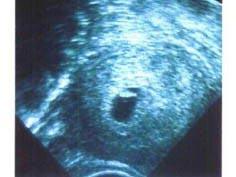

问题 38岁女性,已婚;平素月经规则,周期30天,现停经90余天,阴道少量流血10天。子宫腔内B超结果如图,考虑 ( )

选项 A、难免流产 B、子宫肌瘤 C、葡萄胎 D、稽留流产 E、先兆流产

答案 D